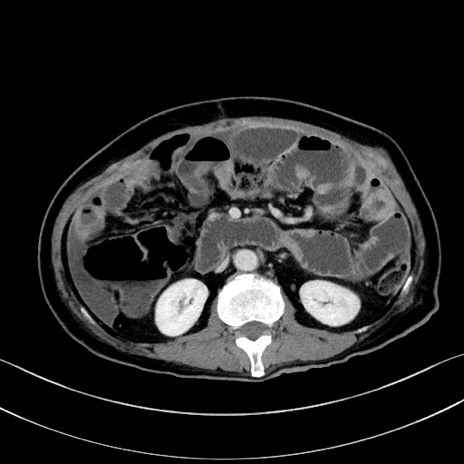

症例28(横断像)

【症例】60歳代男性

【主訴】嘔吐

【現病歴】胃癌にて胃全摘後。食思不振が悪化し、夜中に嘔吐することがある。

【既往歴】胃癌、胃全摘、脾摘、胆摘後

【データ】WBC 5900、CRP 10.56